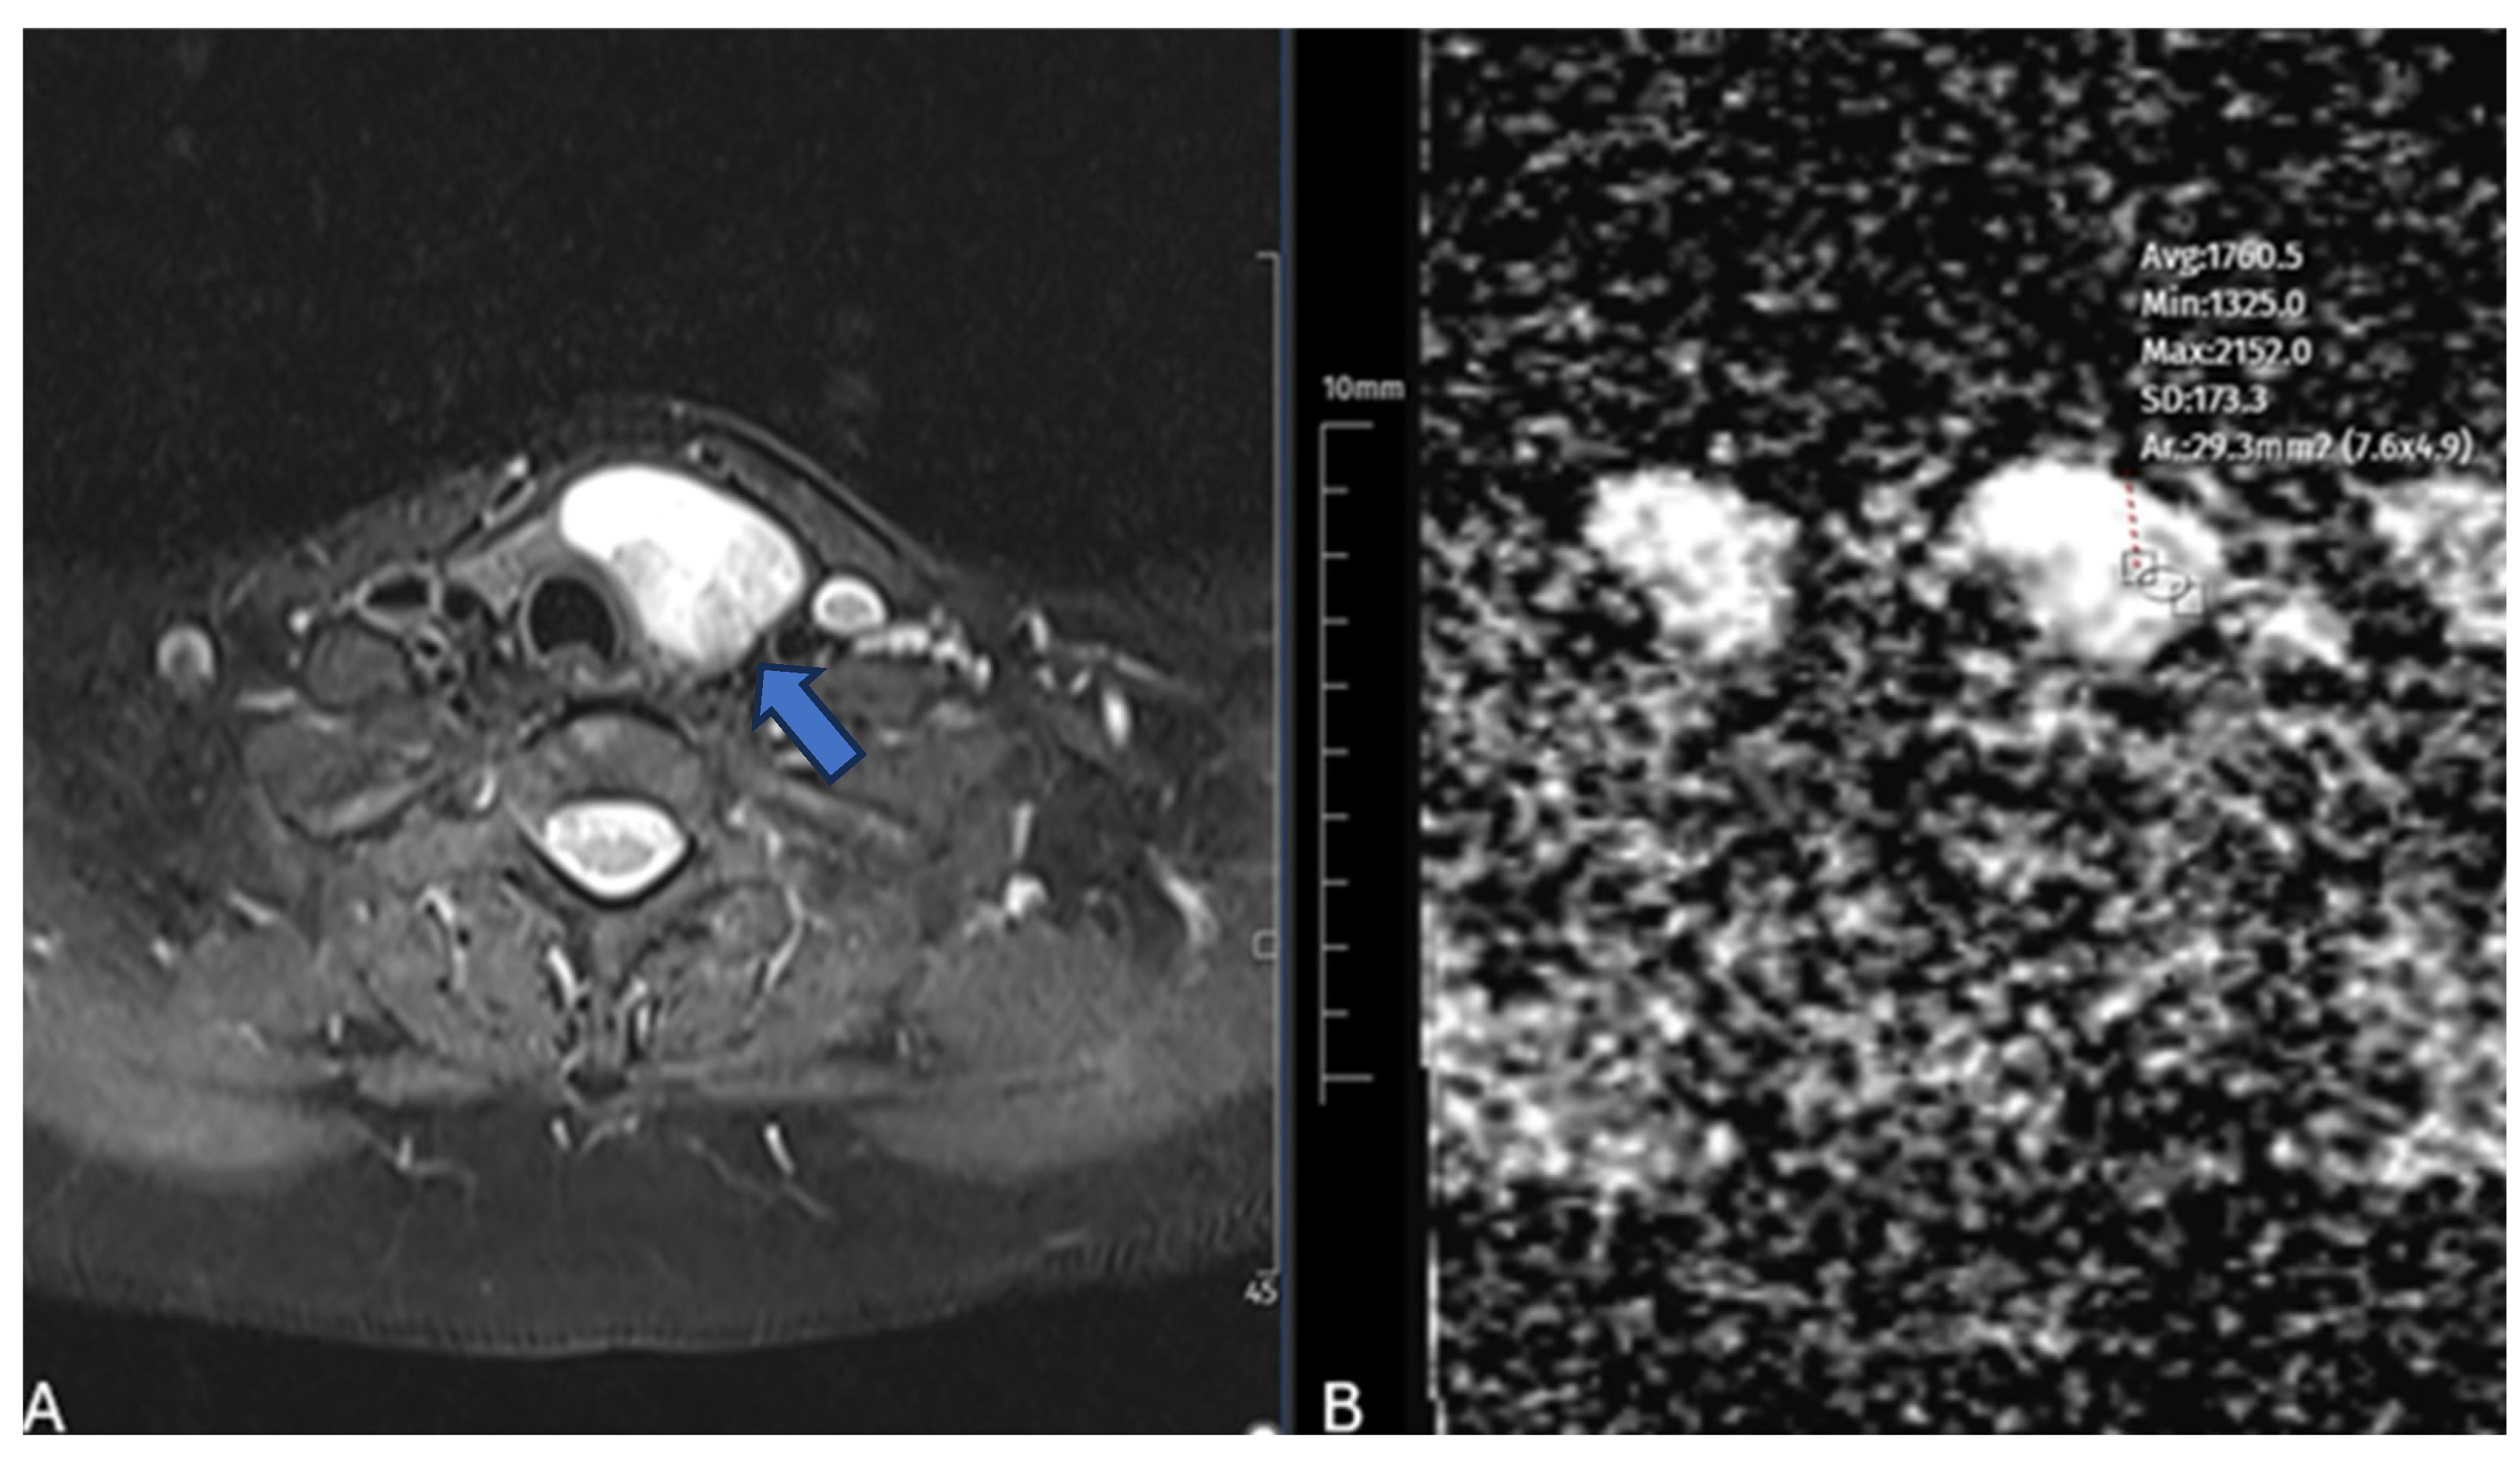

2.2. Diffusion-Weighted MRI Protocol and Analysis